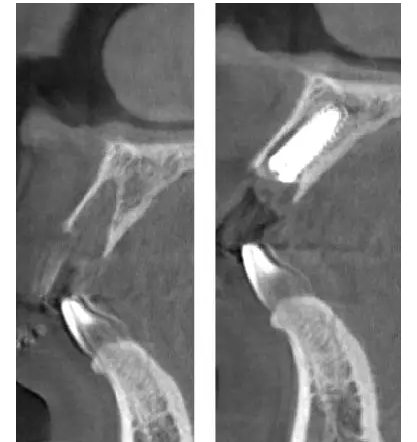

術(shù)前、術(shù)后CT